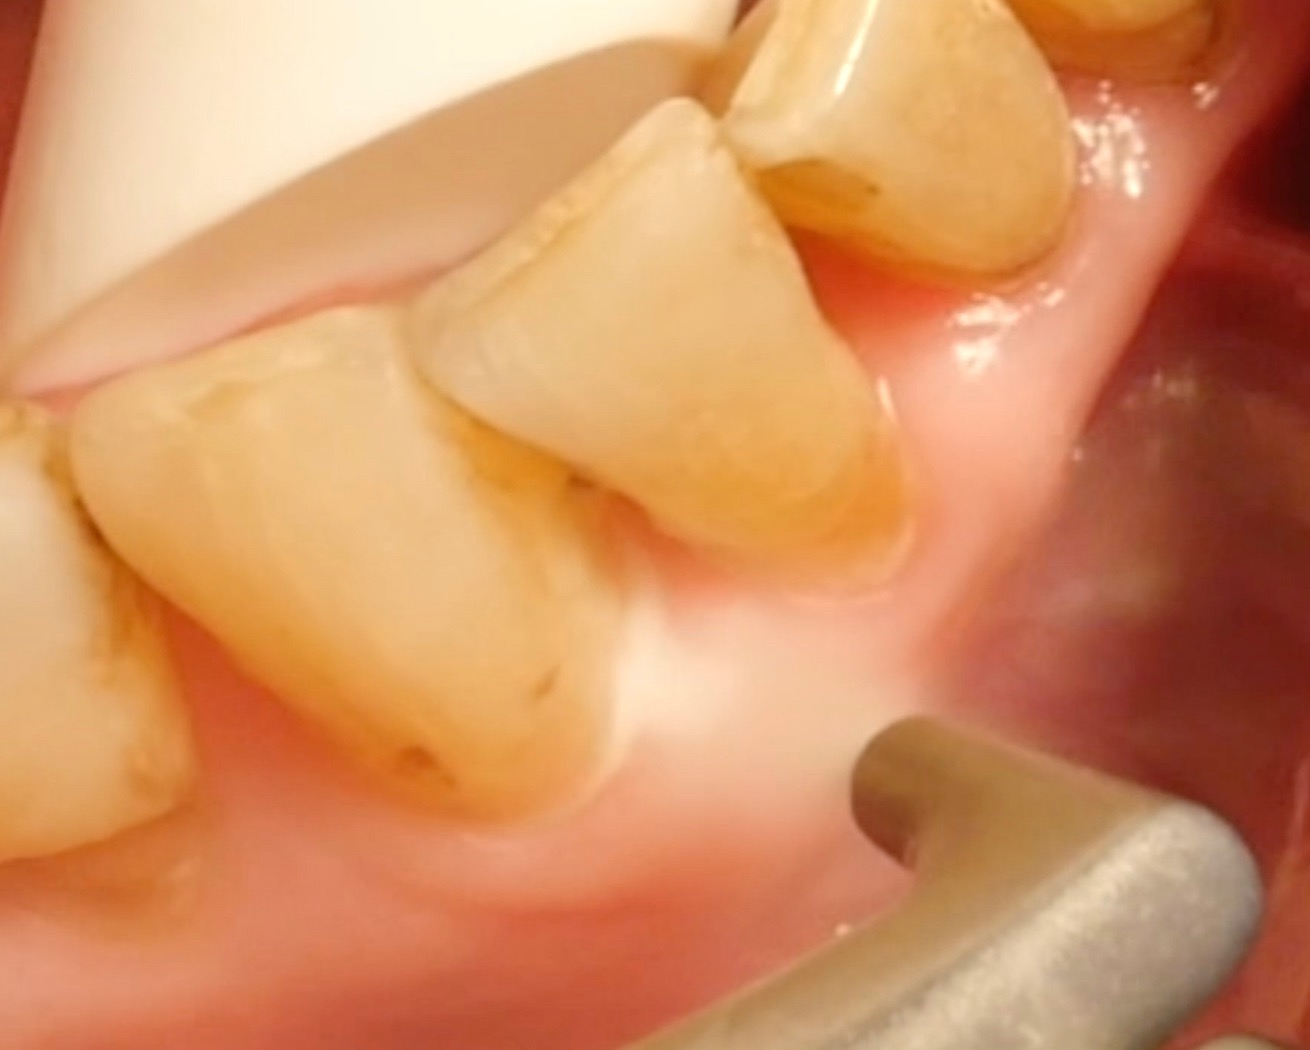

Pulverstrahlgeräte haben sich in der Parodontaltherapie in den letzten Jahren eindeutig etabliert. Doch wie effizient sind sie? Wo liegt deren Einsatzbereich? Was gilt es bei der Anwendung zu beachten?

• Die Biofilmentfernung ist sowohl bei Sondierungstiefen ≤ 4mm als auch bei Sondierungstiefen von 5 bis 9 mm effektiver und schneller gegenüber herkömmlichen Methoden; jedoch das klinische Outcome ist vergleichbar und keine Methode ist eindeutig überlegen.

• Es gilt bei Pulverstrahlgeräten jedoch unbedingt zu beachten, dass Zahnstein- und Konkrement-Ablagerungen nicht abgetragen werden können; hier ist die Kombination mit (Ultra)Schallgeräten und/oder Handinstrumenten notwendig!